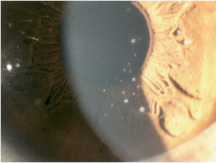

On exam, the vision can vary from 20/20 to hand motion or light perception depending on the amount of corneal epithelial edema, although the amount of edema is usually mild. The pupil is often slightly dilated or sluggish. The conjunctiva is usually white and quiet, although a mild ciliary flush may be present. There may be small-to-medium, discrete, round, white keratic precipitates on the endothelium, usually in an inferior distribution (Figure 2). The KPs usually resolve on their own or with anti-inflammatory treatment. The anterior chamber is deep with a mild iritis without significant cell or flare. In the past, iris atrophy or heterochromia was noted in some cases, but they are not currently considered a characteristic finding for PSS.